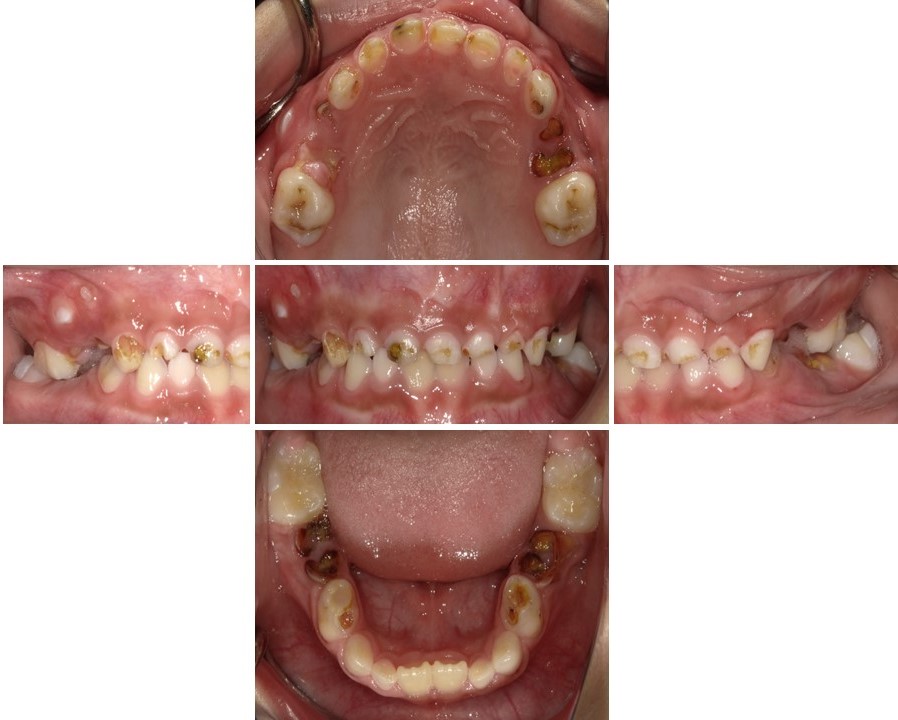

子どものう蝕の数は年々減少しており、う蝕の全くない子どもが多くいますが(図2)、重度のう蝕を有する子どもが一定程度存在し続けています(図3)。3歳まではう蝕がないことが一般的であり、この頃までに既にう蝕がある子どもに対しては、将来的にう蝕リスクが高い対象として、特に配慮していく必要があります。子どものう蝕の発生に影響する要因として口腔清掃不良が挙げられますが、砂糖の摂取に関連した不適切な生活習慣にも注目する必要があります。う蝕になりやすいのは、ほとんど唾液が分泌されず自浄作用が低下する「就寝時」です。そこで、就寝前に適切な口腔清掃を行うことが重要であり、砂糖を含む食品の摂取を控えるように指導してください。

(図2)う蝕のない小児(3歳0か月男児)

(図3)重度のう蝕を有する小児(5歳9か月男児)